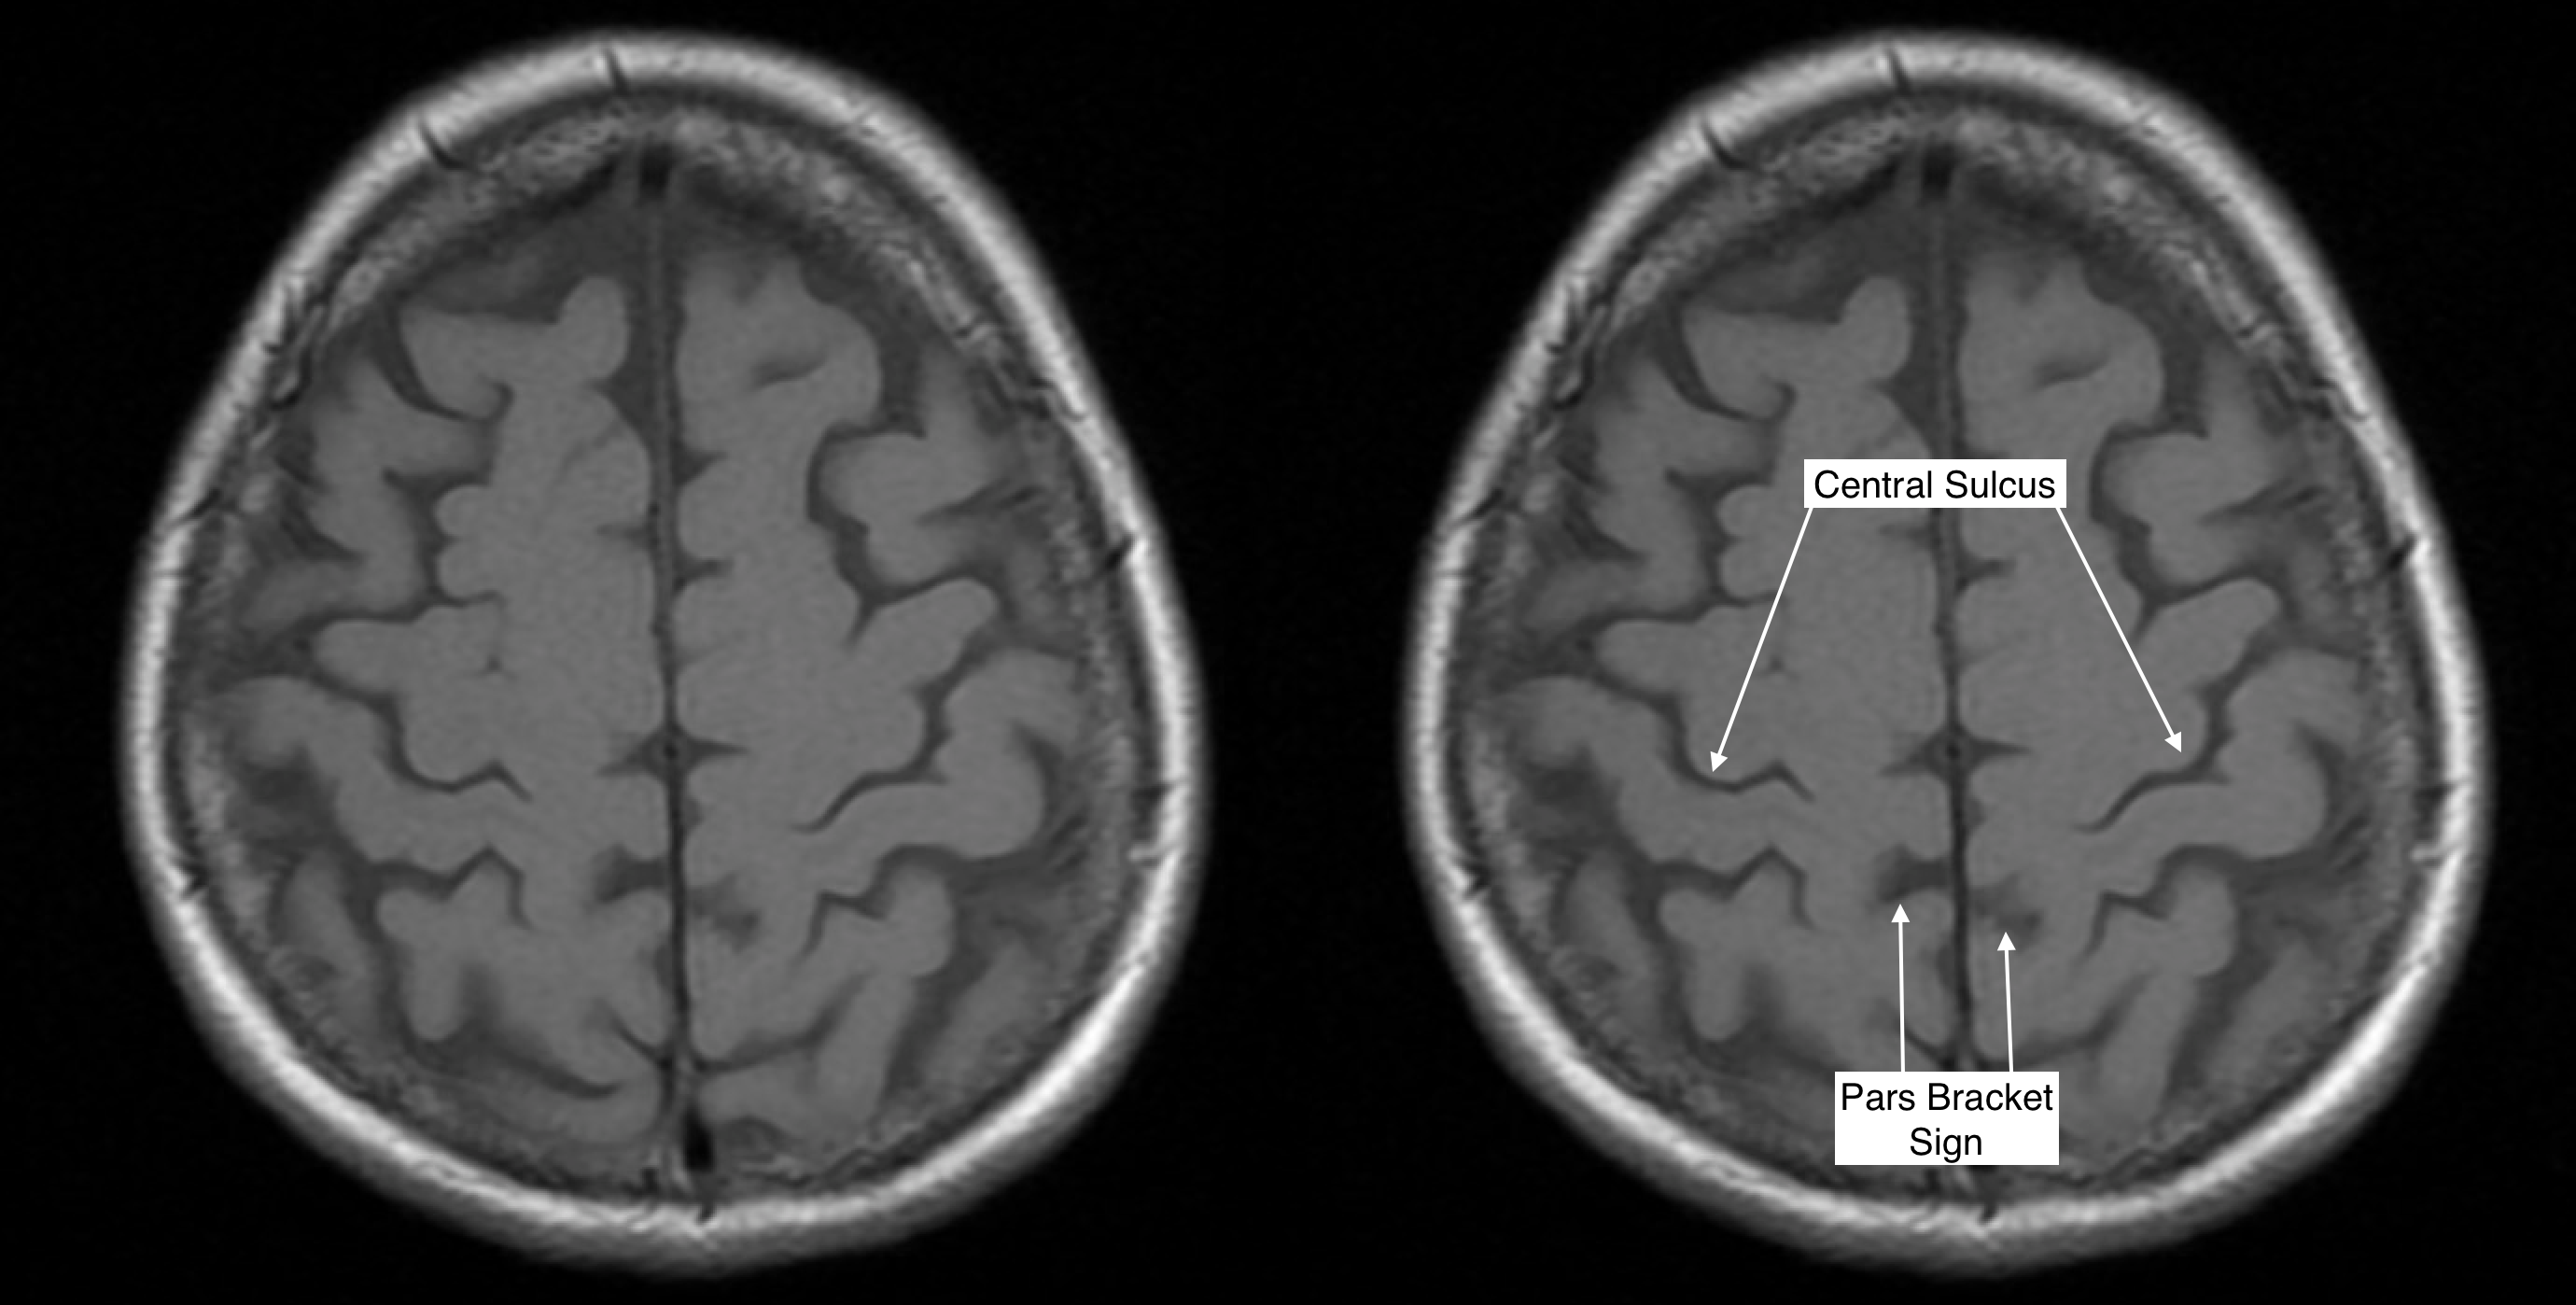

Radiological Anatomy Central Sulcus Stepwards